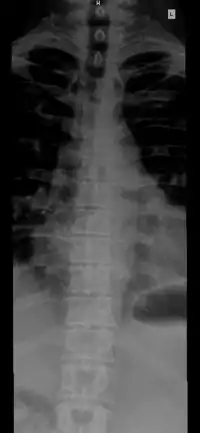

![]() The human vertebral column and its regions | |

The vertebral column, also known as the backbone or spine, is the core part of the axial skeleton in vertebrate animals. The vertebral column is the defining characteristic of vertebrate endoskeleton in which the notochord (a flexible collagen-wrapped glycoprotein rod) found in all chordates has been replaced by a segmented series of mineralized irregular bones (or sometimes, cartilages) called vertebrae, separated by fibrocartilaginous intervertebral discs (the center of which is a notochord remnant).[1] The dorsal portion of the vertebral column houses the spinal canal, a cavity formed by alignment of the neural arches that encloses and protects the spinal cord.

The number of vertebrae in a region can vary but overall the number remains the same. In a human vertebral column, there are normally 33 vertebrae.[3] The upper 24 pre-sacral vertebrae are articulating and separated from each other by intervertebral discs, and the lower nine are fused in adults, five in the sacrum and four in the coccyx, or tailbone. The articulating vertebrae are named according to their region of the spine. There are 7 cervical vertebrae, 12 thoracic vertebrae and 5 lumbar vertebrae. The number of those in the cervical region, however, is only rarely changed,[4] while that in the coccygeal region varies most.[5] Excluding rare deviations, the total number of vertebrae ranges from 32 to 35.[6] In about 10% of people, both the total number of pre-sacral vertebrae and the number of vertebrae in individual parts of the spine can vary.[7][8][9] The most frequent deviations are: 11 (rarely 13) thoracic vertebrae, 4 or 6 lumbar vertebrae, 3 or 5 coccygeal vertebrae (rarely up to 7).[9]

The vertebrae in the human vertebral column is divided into different regions, which correspond to the curves of the vertebral column. The articulating vertebrae are named according to their region of the spine. Vertebrae in these regions are essentially alike, with minor variation. These regions are called the cervical spine, thoracic spine, lumbar spine, sacrum, and coccyx. There are seven cervical vertebrae, twelve thoracic vertebrae, and five lumbar vertebrae.